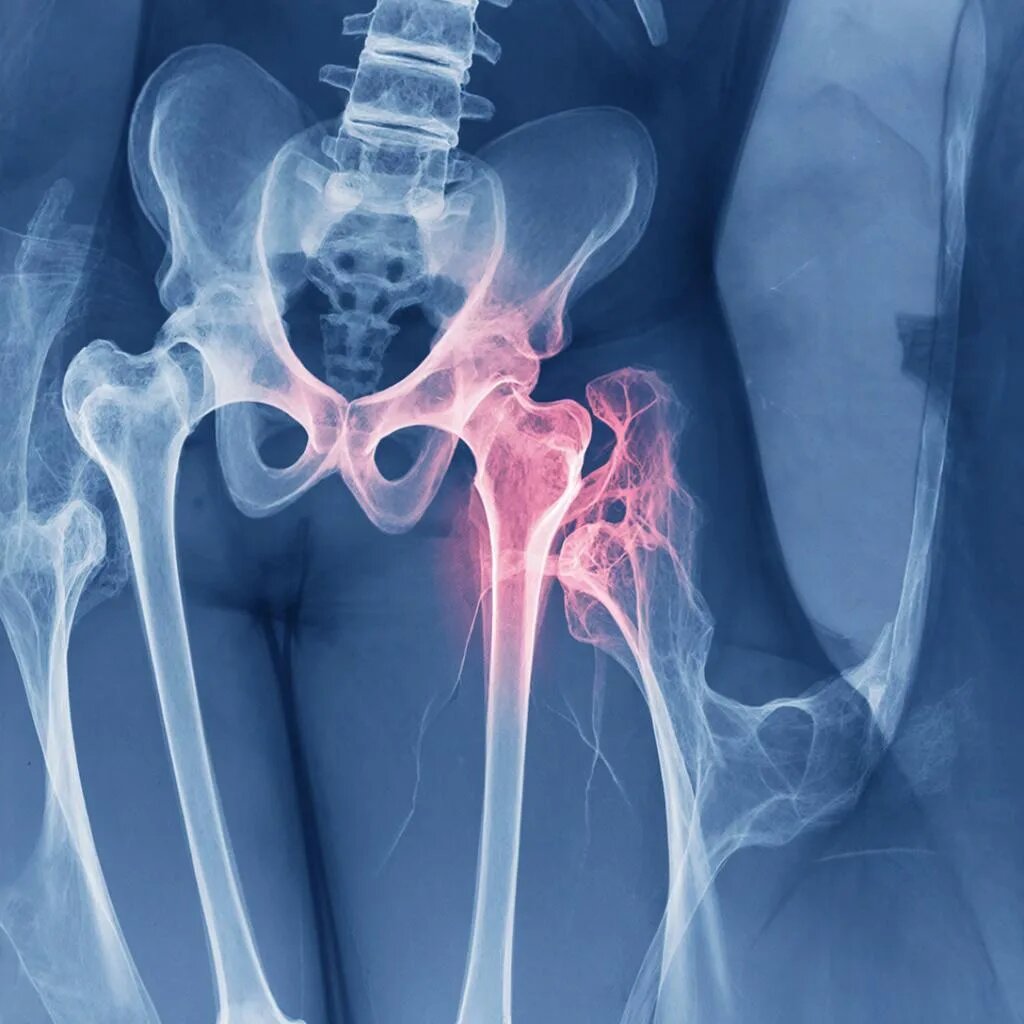

Остеопороз не приговор: 5 идей для ужина, когда диета кажется скучной На приеме пациенты часто жалуются мне на одно и то же: «Доктор, я понимаю, что нужно есть творог и овощи, но это же пресно и быстро надоедает. А так хочется просто вкусно поужинать после работы, не чувствуя себя при этом больным человеком». Это абсолютно нормальное желание. Лечебное питание при остеопорозе — это не тюремная диета. Да, мы вынуждены ограничивать соль, кофеин и продукты, вымывающие кальций (щавель, шпинат, свеклу — в больших количествах, алкоголь). Но наша цель — не просто накормить вас, а дать организму строительный материал для костей и при этом доставить gastronomic удовольствие. Сегодня я поделюсь пятью простыми, но «живыми» рецептами ужинов. Они готовятся из доступных продуктов, не требуют кулинарных подвигов и, главное, помогают усваиваться кальцию и витамину D. Когда мы говорим «рыба», пациенты часто представляют скучное филе на пару. Но давайте добавим креатива.